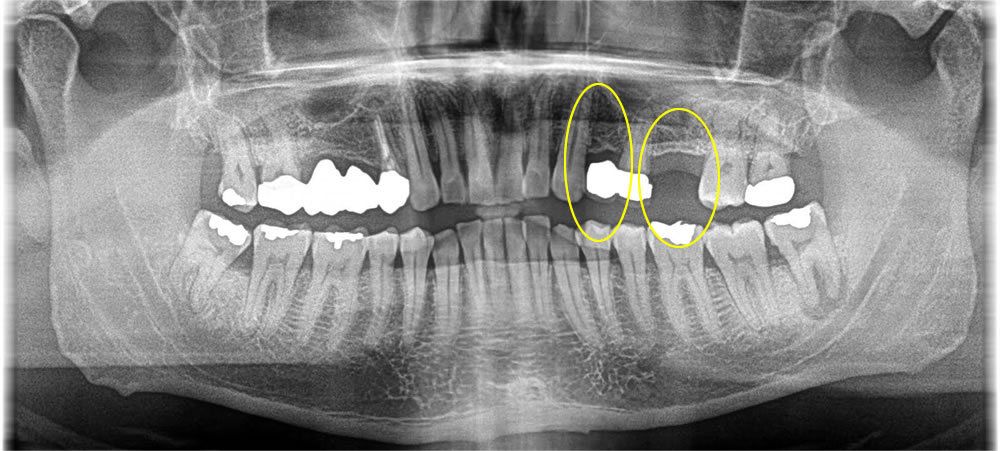

痛みのあるブリッジの歯をインプラントで治療した症例

元々歯のない前歯には、最小限の切開(8ミリ程度)にてインプラントの埋入と共に仮の歯を装着し、見た目も即日で回復していきました。

また、奥の歯はCT写真にて骨が弱っていたため、しっかりと歯茎を切開し、骨の状態を確認しながら施術を行っていきました。